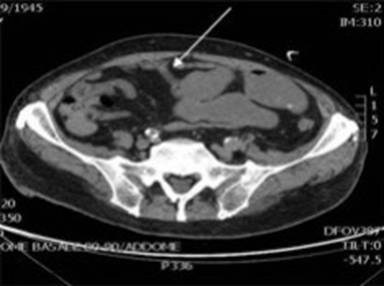

A contrast-enhanced abdominal CT scan showed a stenosis of the small bowel (Figure 2). We decided for an explorative laparotomy. During the procedure we observed no free fluid or blood; there were some loose visceral adhesions and no signs of mesenteric ischemia.

Figure 2. Stenosis of the small bowel (arrow). |